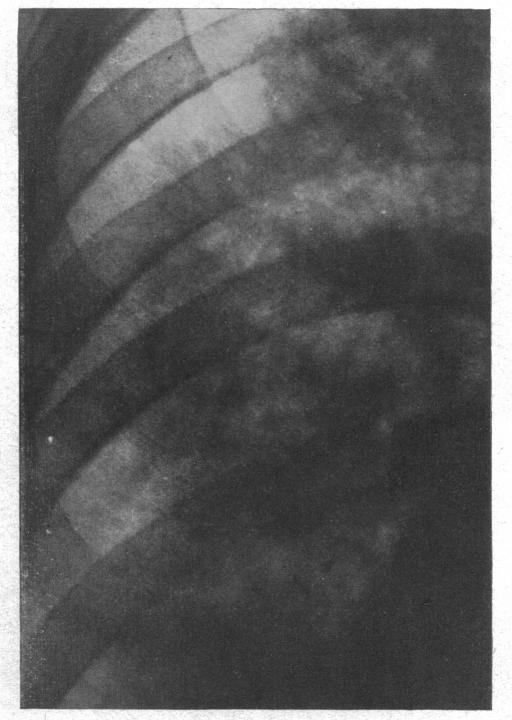

The radiology of acute pulmonary oedema.

Br Heart J. 1951 Oct;13(4):503-18. doi: 10.1136/hrt.13.4.503.